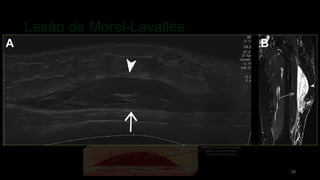

Lesão de Morel-Lavallée

• #29 A consequência potencial do trauma de alta energia é uma lesão de Morel-Lavallée. Essa condição é causada pelo descolamento da fáscia do tecido subcutâneo sobrejacente por excesso de tensão de cisalhamento com consequente acúmulo de coleção de líquido hemolinfático que classicamente ocorre na face lateral da coxa proximal e joelho. As lesões de Morel-Lavallée podem ser facilmente identificadas por meio de US ou RM. Na US, foi observada uma coleção compressível hiperecóica (fase aguda) ou anecóica (fase subaguda) na interface entre a gordura subcutânea na fáscia muscular. Na RM, a lesão apresenta um sinal T2 heterogêneo na fase aguda e um sinal de hipersinal T2 na fase subaguda. Os contornos são mal definidos na fase aguda e melhor delimitados à medida que a lesão se torna subaguda e crônica. A aspiração guiada por US pode ser realizada para diminuir o volume da coleção de fluido; no entanto, a recidiva é muito comum devido à impossibilidade de realizar uma bandagem compressiva na pelve e ao caráter altamente exsudativo dessa lesão.